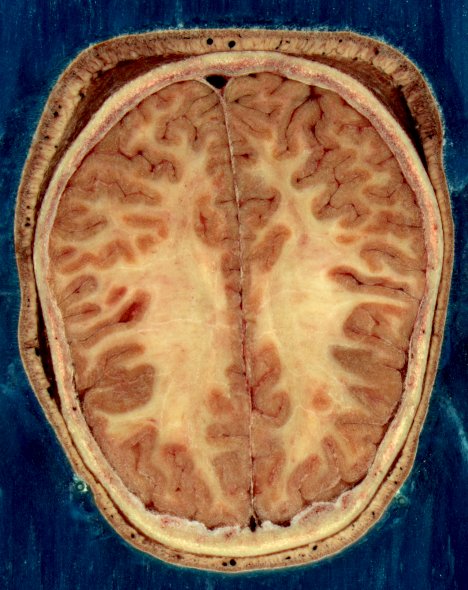

중추신경계는 뇌와 척수로 이루어진 신경계이다. 척주관은 척수를 포함하고, 두개강은 뇌를 포함한다. 중추신경계는 질긴 가죽과 같은 바깥층인 경막을 포함하는 3층 막 시스템인 수막에 의해 둘러싸여 보호된다. 뇌는 또한 두개골에 의해 보호되고 척수는 척추에 의해 보호된다.척추동물(인간 포함)의 신경계는 중추신경계(CNS)와 말초신경계(PNS)로 나뉜다. 중추신경계는 주요 분할이며, 뇌와 척수로 구성된다. 사람의 경우 특히 대뇌가 크게 발달해 있다.[47] 조직은 신경 조직이라고 불리며, 실제로 정보 전달을 수행하는 뉴런과 그 사이를 채우면서 수배나 존재하는 신경교세포 (글리아 세포)나 희소돌기아교세포, 별아교세포 등으로 구성된다.[48]

척추동물 신경계는 회백질과 백색질이라고 불리는 영역으로도 나눌 수 있다. 회백질은 뉴런의 세포체 비율이 높고, 백색질은 주로 수초가 있는 축삭으로 구성되어 있으며, 수초에서 색상을 얻는다. 백색질은 모든 신경과 뇌 및 척수의 대부분의 내부를 포함한다. 회백질은 뇌와 척수의 뉴런 덩어리와 표면을 따라 늘어선 피질층에서 발견된다. 뇌나 척수의 뉴런 덩어리를 핵(신경해부학)이라고 부르고, 말초의 뉴런 덩어리를 신경절이라고 부르는 해부학적 관습이 있다.